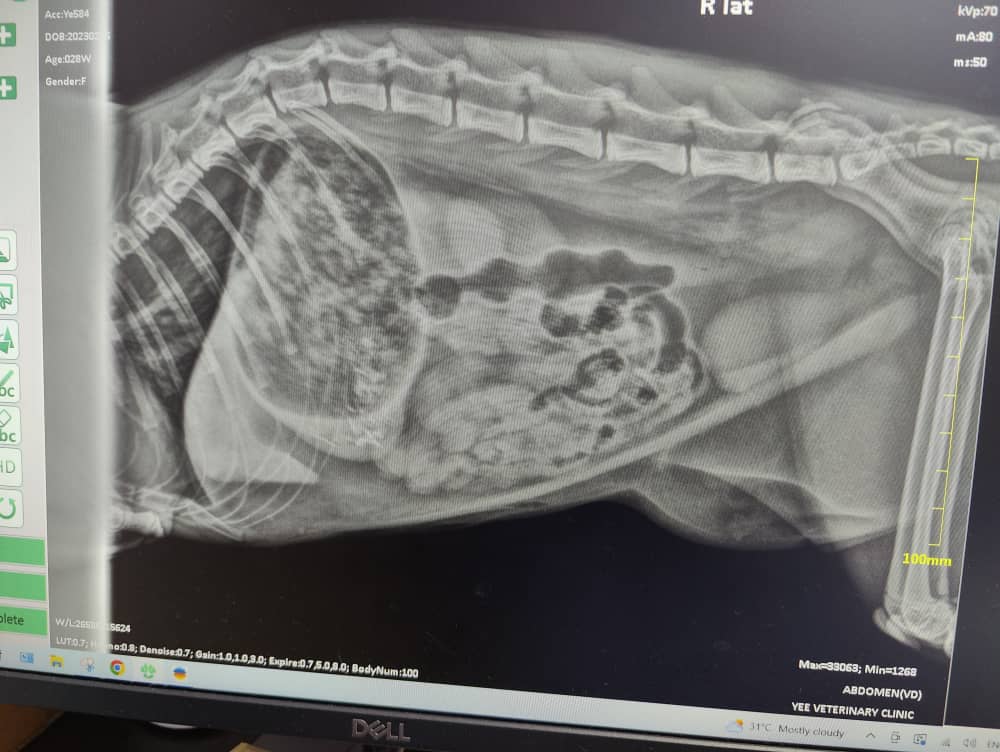

Two X-Rays were taken and it showed plication. This means corrugation or folds at what appears to be the duodenum (the first part of the small intestines). This is likely caused by the remaining string.

And it also showed that her stomach is full of food.

No 1 is the plication (folds) which is due to the remaining string.

No 2 shows her stomach which is full of food.

No 3 shows the faeces yet to be eliminated.